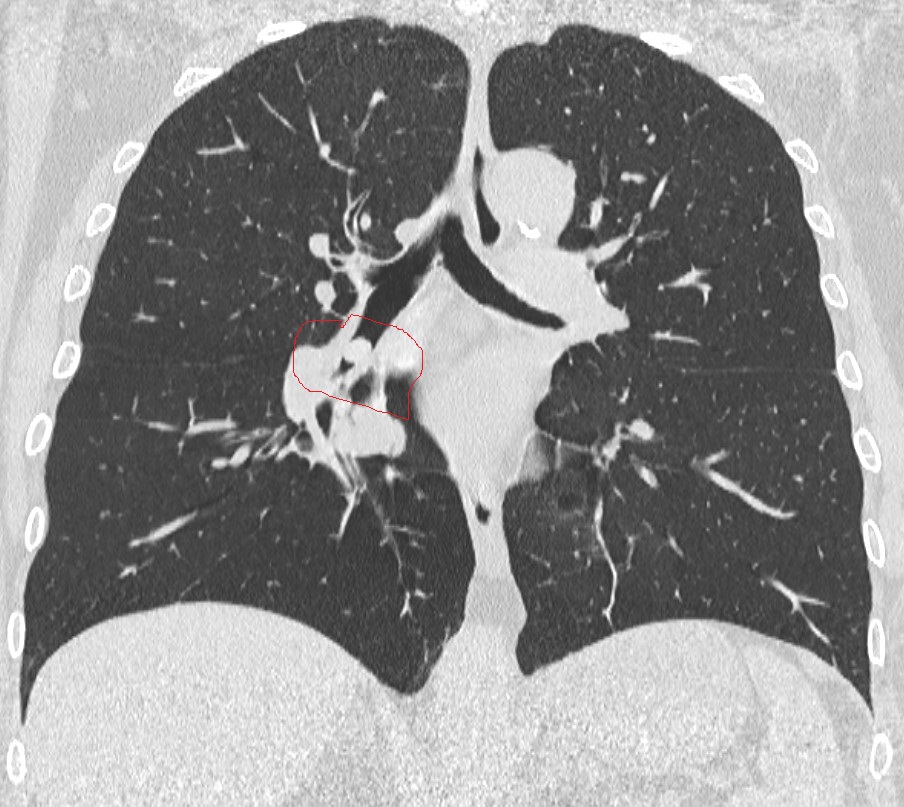

La paziente era arrivata in ospedale con gravi difficoltà respiratorie e una tosse insistente insorta improvvisamente durante il pranzo. Il personale dell’Emergenza-Urgenza ha immediatamente preso in carico la donna, sottoponendola a una serie di accertamenti diagnostici. La radiologa di turno, dott.ssa Chiara Ragone, ha eseguito una TAC toracica che ha evidenziato un’ostruzione subtotale del bronco inferiore del polmone destro, dovuta alla presenza di un sospetto corpo estraneo.

La paziente è stata quindi trasferita con urgenza in sala di Endoscopia Toracica, dove, in anestesia locale, è stato eseguito un intervento di videobroncoscopia flessibile. Utilizzando una pinza a cestello, i medici hanno rimosso con precisione il corpo estraneo: un seme di cece che, inalato accidentalmente, si era conficcato nel bronco inferiore, causando una quasi totale ostruzione delle vie aeree.